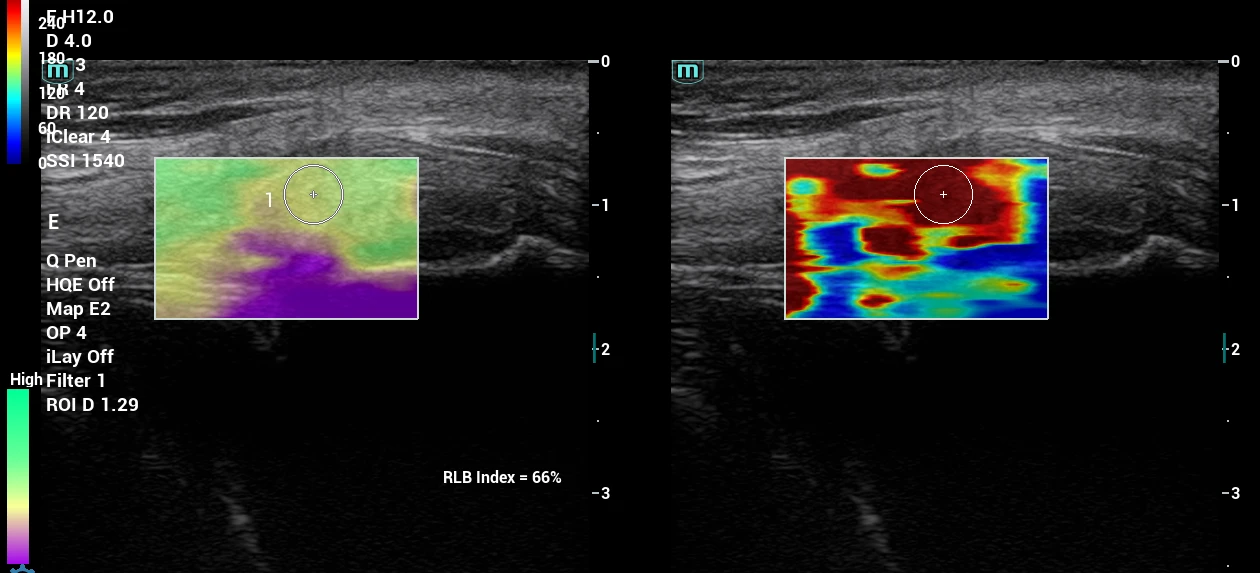

Jednou z najpodstatnejších je inovácia v diagnostických postupoch pri vyšetrení a ošetrení svalových štruktúr v oblasti celého tela, panvy a svalov panvového dna. Objektivizáciou funkcie svalov panvového dna a vybraných svalov trupu prostredníctvom 2D a 3D/4D ultrazvukového vyšetrenia získame komplexnejší pohľad na problém a dokážeme efektívnejšie navrhnúť vhodnú liečbu.